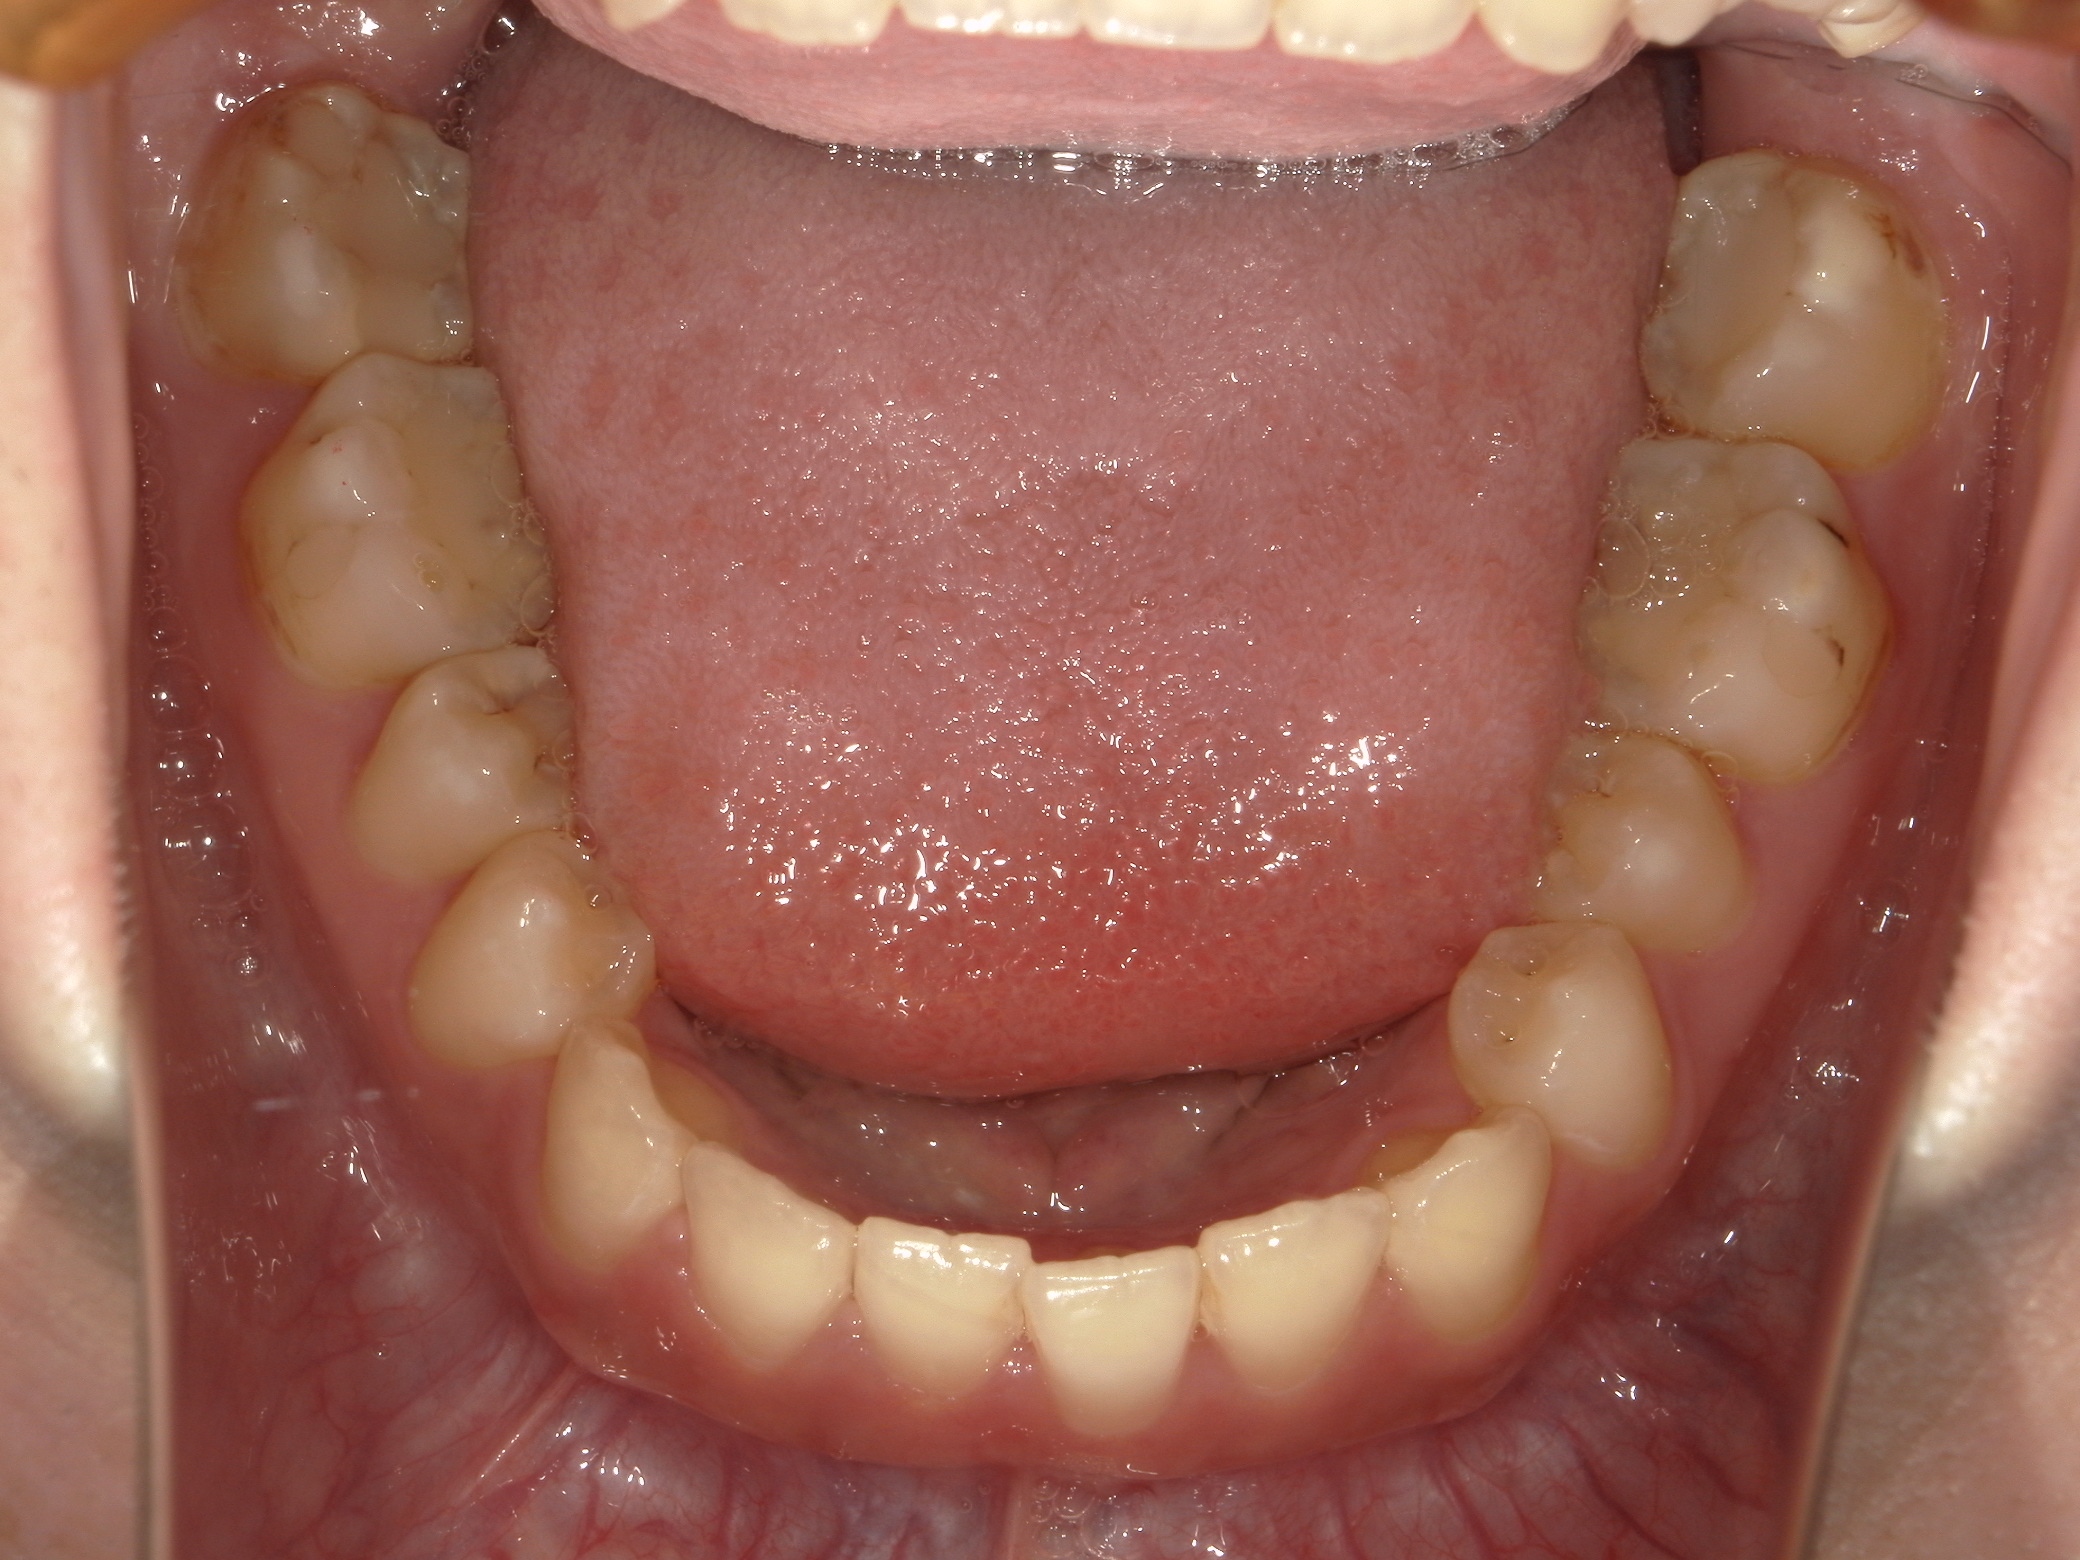

口内下

治療前

治療後